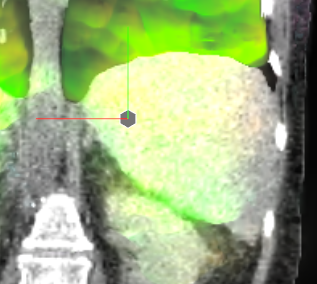

The mean DICE coefficients of the single-atlas registration of the liver and lung masks to the new static patient yield satisfying values of 0.860.12 and 0.960.09. Note the clearly different scan ranges of the data sets (Fig. 2a). The animation of the relevant structures is shown as an example in Fig. 3, using a variable real breathing signal of the target patient (Fig. 2b). In the puncture-relevant liver region, the patient’s breathing states are simulated plausibly for the 4D reference patient (Fig. 3) and, more importantly, the 3D patient (Figs. 4, 5), to which the motion model of was transferred333Demo movie, click here.

We achieve qualitatively plausible results for the liver area in this feasibility study. In the upper thorax especially at the rib cage in neighborhood to the dark lungs stronger artifacts can occur (Fig. 5c). They are due to problems in the inter-patient registration that is a necessary step for the transfer of the motion model. The non-linear deformation sometimes is prone to misaligned ribs. The same is true for the lower thorax with perforation first of the liver and then diaphragm (Fig. 4c). Further optimization have to be carried out as artifacts can appear on the high contrast lung edge (diaphragm, ribs) with a small tidal volume. For liver punctures only, the artifacts of smeared ribs are minor as can be seen in Fig. 4.